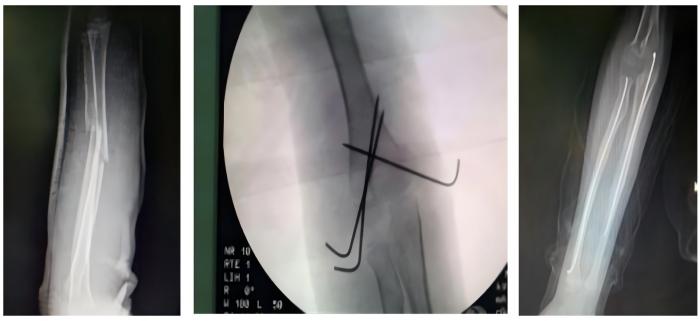

骨科通过几个1-2CM的手术切口,闭合复位骨折,微创插钉,不破坏骨折端软组织及血运。不但减小了手术创伤,还提高了愈合速度。④跳蛋视频

骨折的微创固定手术